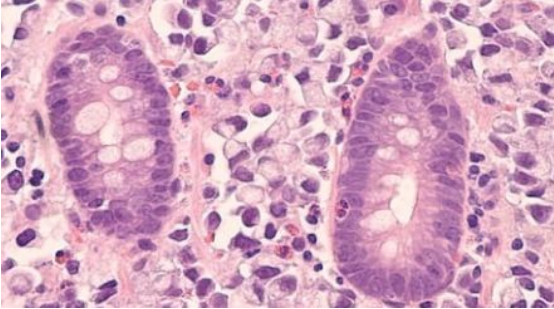

干細(xì)胞歸巢是指內(nèi)源或外源性干細(xì)胞在多種因素的作用下,能定向趨向性遷移,越過(guò)血管內(nèi)皮細(xì)胞至靶向組織并定植存活的過(guò)程,類似人體局部炎癥反應(yīng)后大量白細(xì)胞遷移至炎癥周圍。

血管中的 MSCs 黏附于毛細(xì)血管壁跨內(nèi)皮細(xì)胞層歸巢至目標(biāo)組織,MSCs和細(xì)胞外基質(zhì)通過(guò)表達(dá)細(xì)胞黏附分子配體與細(xì)胞黏附分子結(jié)合,介導(dǎo)干細(xì)胞歸巢到特定的靶點(diǎn)。